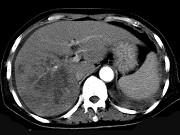

问题 男,42岁,中上腹痛,轻度黄疸,结合CT图像,提出最可能的诊断()

选项 A.肝脓肿 B.肝多发性囊肿 C.肝癌肝内转移伴门脉癌栓形成 D.胆管细胞癌 E.肝血管瘤

答案 C